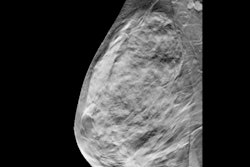

Researchers have touted DBT as a promising method in improving lesion characterization, with lower false-positive rates and higher cancer detection rates for all age groups and across all mammographic breast densities. Therefore, Taylor-Cho et al wanted to explore the long-term outcomes and utility of DBT in workup of focal breast pain, taking mammographic breast density and breast cancer risk into consideration.

They looked at data collected between 2014 and 2017 from 91 women who were imaged with DBT and ultrasound for evaluation of focal breast pain. Of these, 16 women (18%) demonstrated findings on imaging, all of which were benign. One case was detected by DBT only, 14 were detected by ultrasound only, and one was detected by combining DBT with ultrasound. Ultrasound resulted in three benign biopsies, the study authors found.

Of the 91 women in the study, 89 had no cancers detected at the site of pain on ultrasound and DBT. DBT also detected two incidental cancers not associated with pain. DBT and ultrasound also agreed that there was no finding at the site of pain in 75 out of 91 cases.